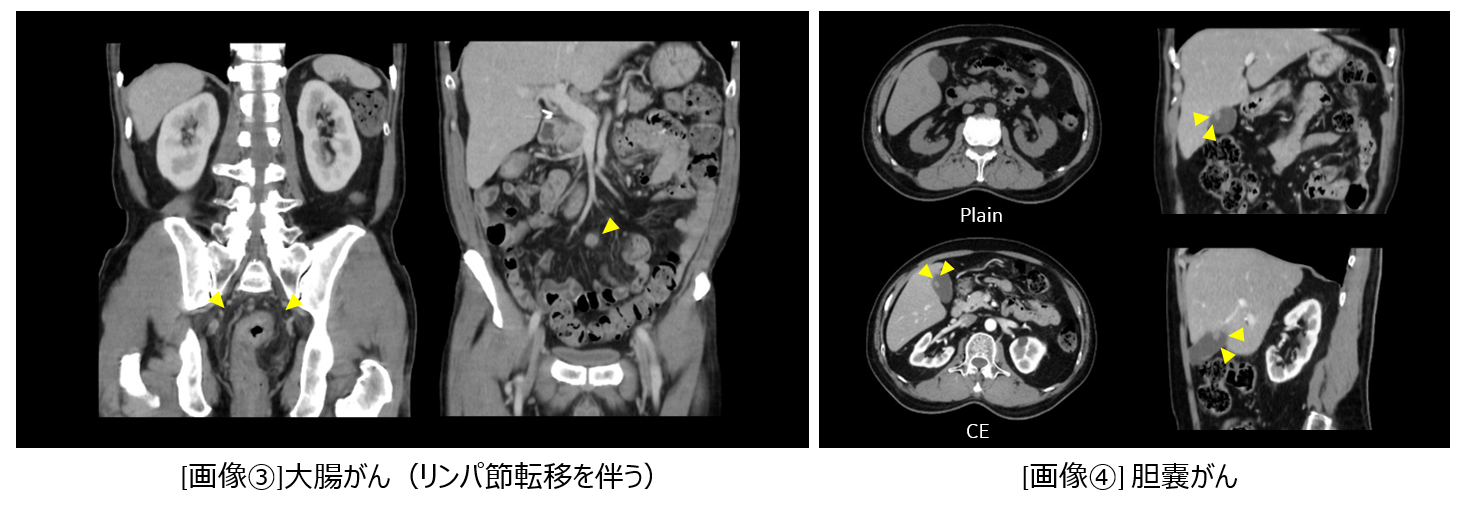

大腸がん(リンパ節転移を伴う) [画像③]、胆嚢がん [画像④]、横行結腸がん狭窄によるイレウス[画像⑤]、カンピロバクター腸炎によるリンパ節肥大 [画像⑥]などの消化器領域病変を検査できています。消化器領域以外では目眩を訴える患者様の頭部を撮影したところ小脳部分に出血を認めました。 [画像⑦]

actcv_sakamoto_naika_0405_big.png

actcv_sakamoto_naika_060708_big.png